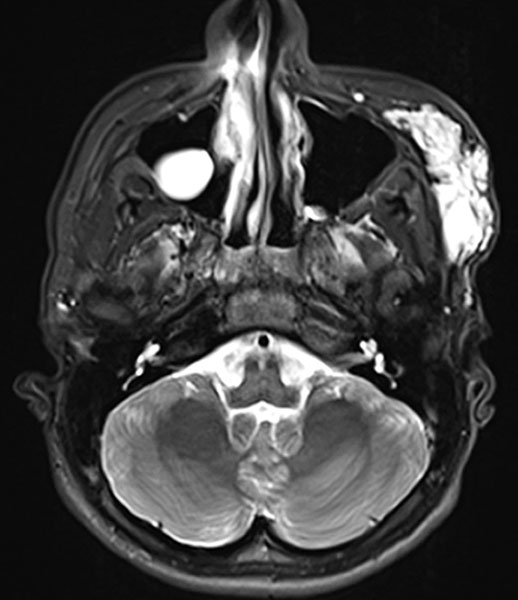

Axial, T2-weighted fat-suppressed MRI of the face. The venous malformation appears typically very hyperintense here too. No expansion into the depth.